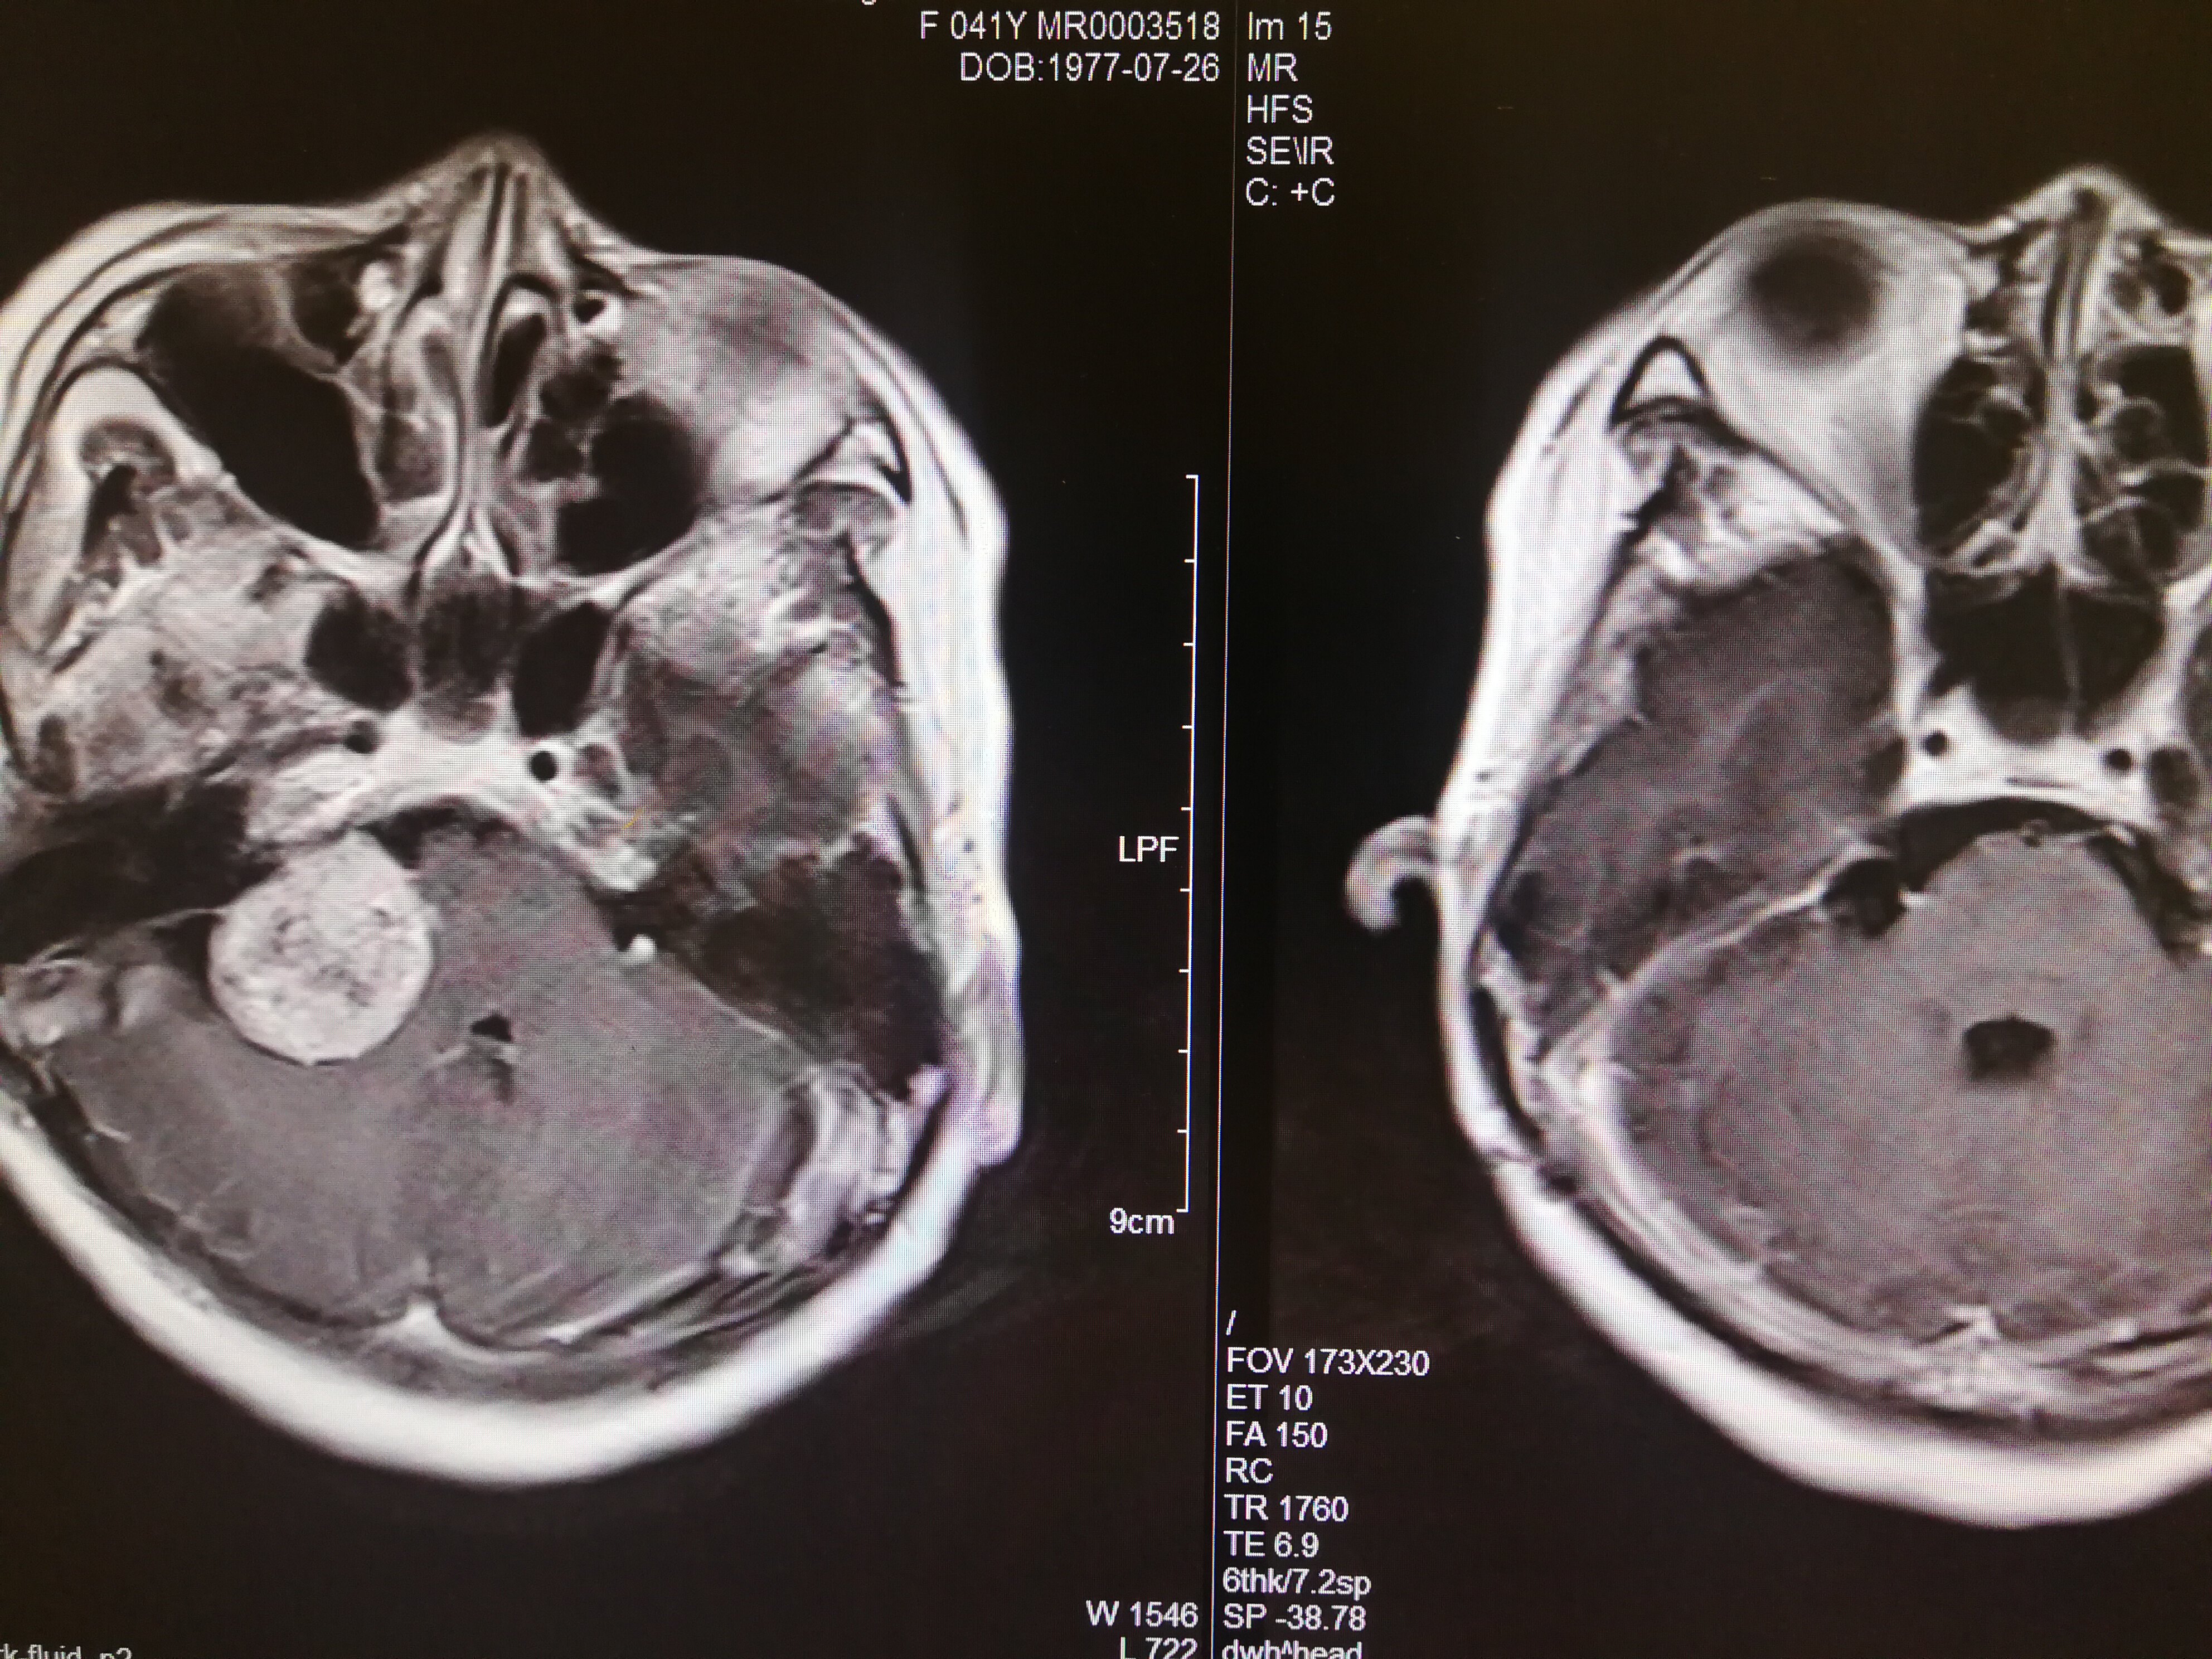

手术治疗听神经瘤是最主要的治疗方式,目前听神经瘤的手术已经非常成熟,只要没有明显的手术禁忌症首先应考虑手术治疗,并要求在电生理监测条件下完成手术,这样可以最大限度地保护面神经功能。以下是几例我们做的听神经鞘瘤手术前后核磁共振片子对照,除手术后听力不能恢复外,没有面瘫,脸部麻木,吞咽困难等颅神经症状,也无其他较明显的手术并发症发生。